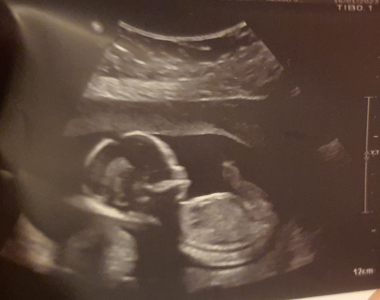

Nastávající maminka Broňka má zálibu v DJingu, stejně jako její přítel, se kterým očekávají narození prvního dítěte. Na první těhotenskou kontrolu šla...